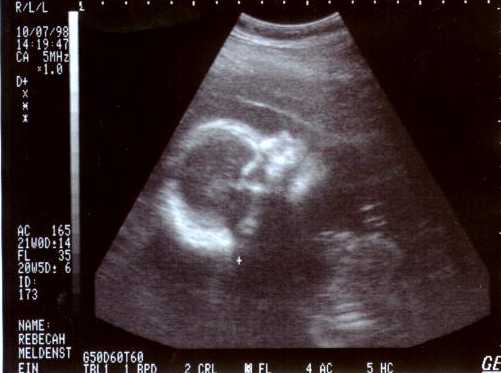

This is my 22 weeks & 6 day Ultra Sound Picture, It's pretty clear huh?!!